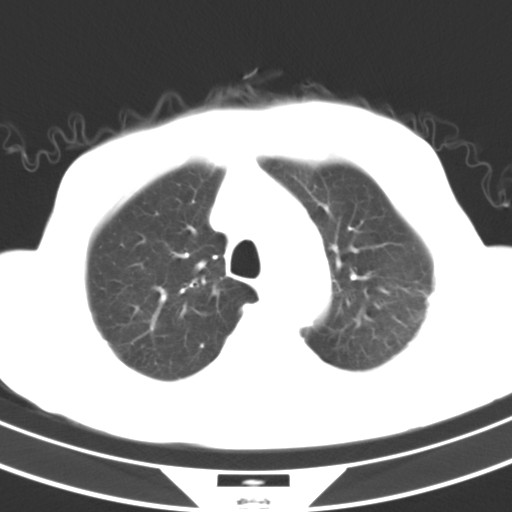

标题: CT18248:男,71岁,糖尿病住院,无发热、咳嗽、咳痰。 [打印本页]

男,71岁,糖尿病住院,无发热、咳嗽、咳痰。

1)两肺感染性病变(结核可能性大)。2)左肺上叶近纵隔胸膜下肺大泡。

1)两肺继发性结核。2)左肺上叶近纵隔胸膜下肺大泡。